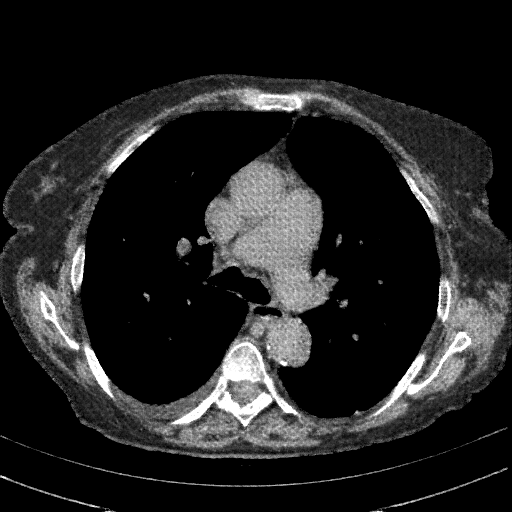

Targeted Slice 70 - Mediastinum Window Analysis (Generated vs Real Venous)

0.625

Mediastinum SSIM

56.4

Mediastinum RMSE

25.0

Mediastinum MAE

Average Mediastinum Window Metrics Across All Slices (153 slices) - Generated vs Real Venous

0.556

Mediastinum SSIM (Avg)

58.5

Mediastinum RMSE (Avg)

29.2

Mediastinum MAE (Avg)

Original VENOUS CT scan

Mediastinum window (WL 40, WW 400 β†’ Low βˆ’160, High +240)

Actual HU range: [-160.0, 240.0]